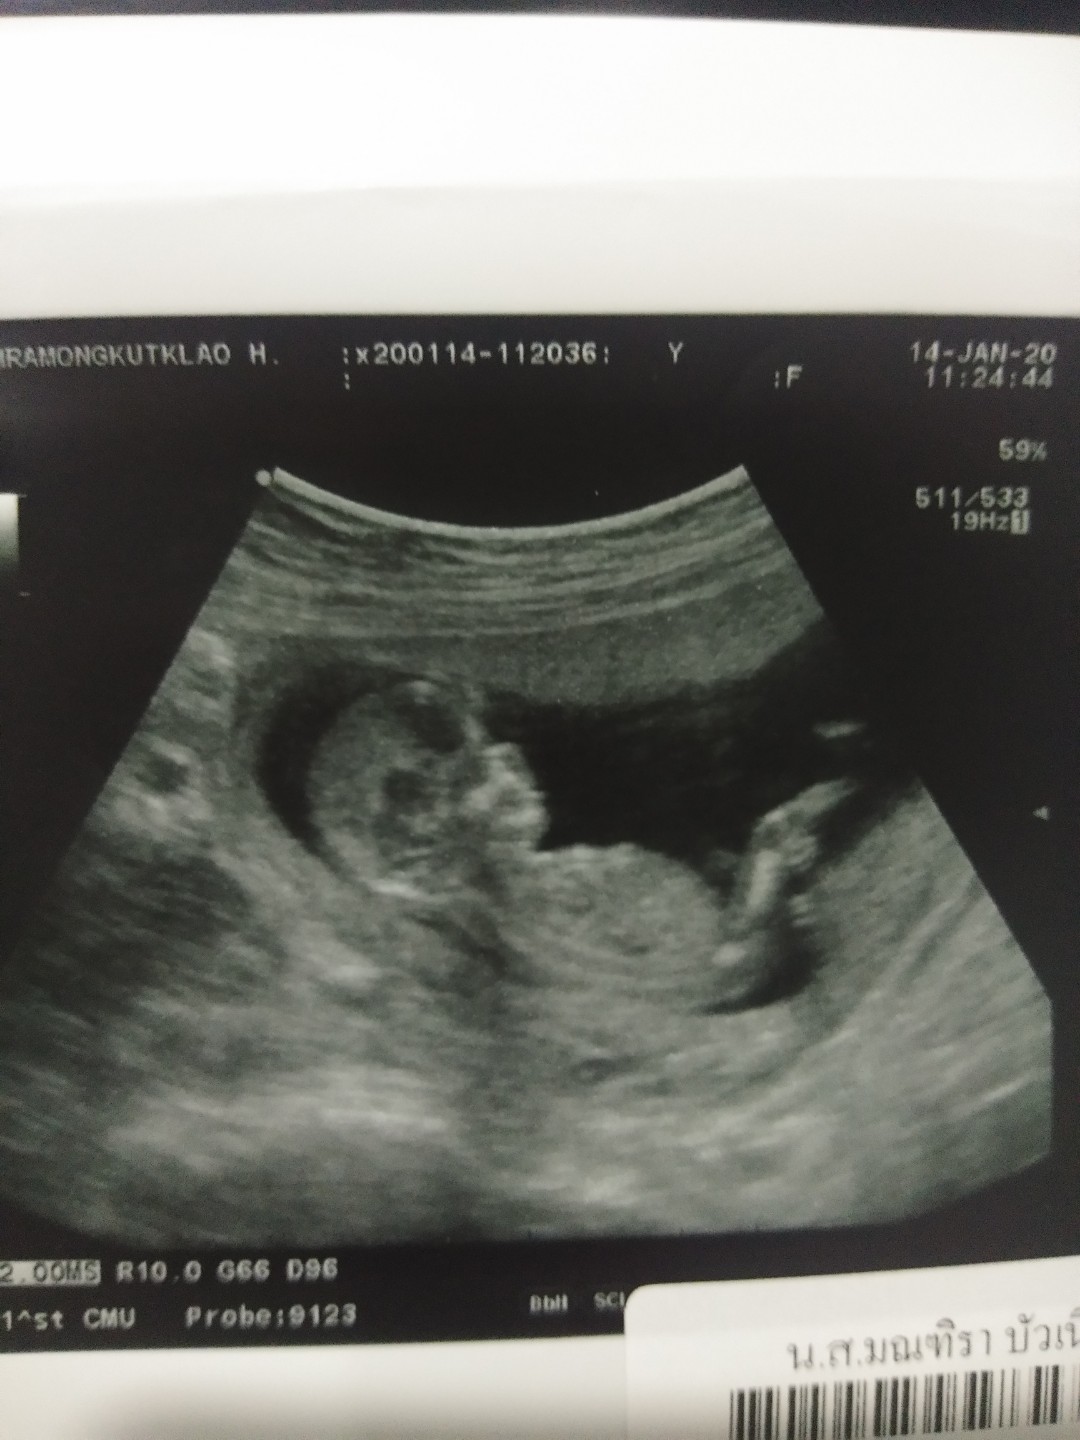

12 week ka

12 วีค4วันจ้า

12วีคค่ะ💕

ตอน12wค่ะ

12วีคค่ะ

12w2d จ้า